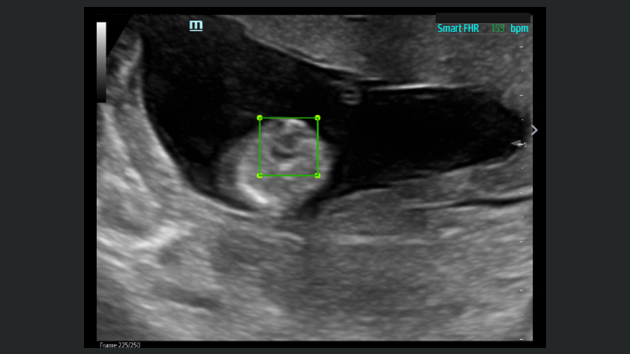

Obrazy kliniczne